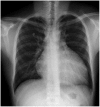

Pneumopericardium is a rare complication of pericardiocentesis, occurring either as a result of direct pleuro-pericardial communication or a leaky drainage system. Air-fluid level surrounding the heart shadow within the pericardium on a chest X-ray is an early observation at diagnosis. This clinical measurement and process is variable, depending on the hemodynamic status of the patient. The development of a cardiac tamponade is a serious complication, necessitating prompt recognition and treatment. We recently observed a case of pneumopericardium after a therapeutic pericardiocentesis in a 20-year-old man with tuberculous pericardial effusion.